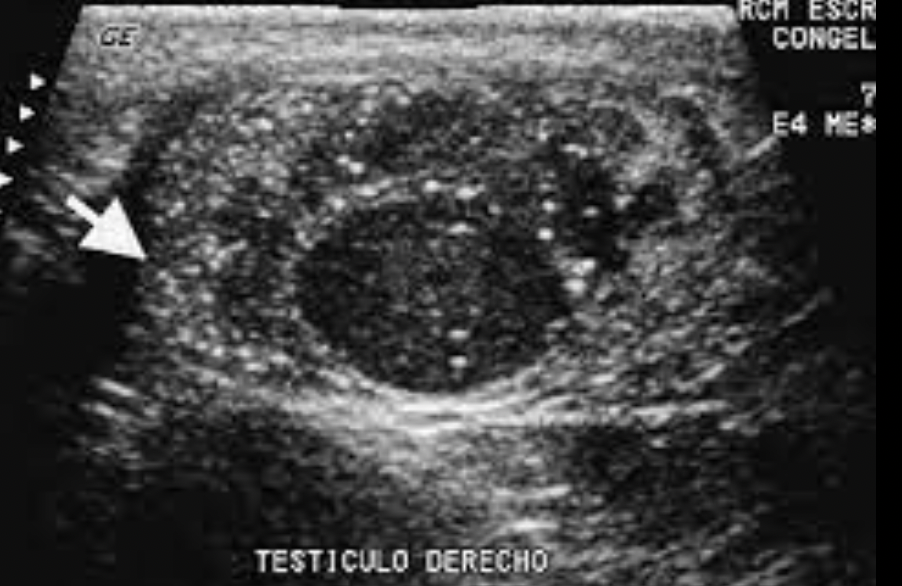

Dx imagen

A

USG escrotal

12

Q

como se ve al USG escrotal ??

Imagen heterogénea en el parénquima testicular

(el testÍculo normal es homogeneo)